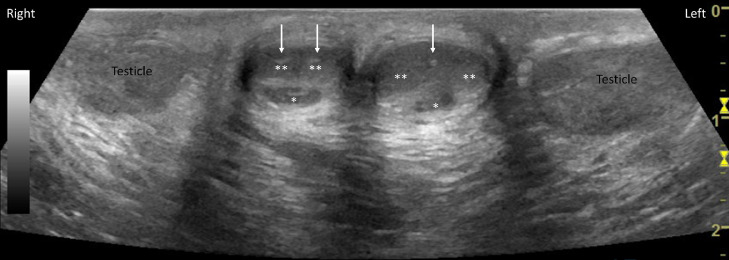

Ultrasound of the penis and scrotum (Fig. 2) demonstrated well-developed right penis, with normal corpora spongiosum and normal separate corpora cavernosa each supplied by separate cavernosal artery. Left penis demonstrated normal corpora spongiosum, and 2 separate corpora cavernosa supplied by 1 cavernosal artery. Undescended well-developed testes were also seen in the inguinal canal (Fig. 3). Doppler imaging demonstrated normal flow to both the testes.

Fig. 2.

Ultrasound of the penis and scrotum demonstrates well-developed right penis, with normal corpora spongiosum (*) and normal separate corpora cavernosa (**) each supplied by separate cavernosal artery (white arrow). Left penis demonstrated normal corpora spongiosum (*), and 2 separate corpora cavernosa (**) supplied by one cavernosal artery (white arrow).